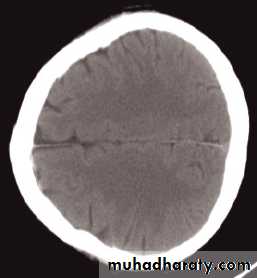

The cardinal signs of an abnormality on a CT scan are:

• Abnormal tissue density• Mass effect

• Enlargement of the ventricles.

Abnormal tissue density

• Abnormal tissue may be of higher or lower density than the normal surrounding brain.• High density is seen with recent haemorrhage, calcified lesions, and areas of contrast enhancement

• Low density is usually due to neoplasms or infarcts, or to oedema, which commonly surrounds neoplasms, infarcts, haemorrhages and areas of inflammation.

Mass effect

• The lateral ventricles should be examined to see if they are displaced or compressed.• Shift of midline structures, such as the septum pellucidum , the third ventricle, or the pineal, is a common finding with intracranial masses.

Enlargement of ventricles

There are two basic mechanisms which cause the cerebral ventricles to enlarge:• Obstruction to the CSF pathway, either within the ventricular system (non-communicating hydrocephalus) or over the surface of the brain (communicating hydrocephalus)

• Secondary to atrophy of brain tissue